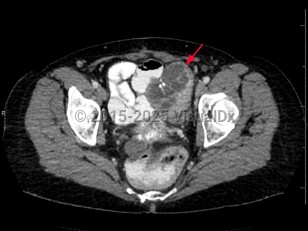

Uterine fibroidsUterine fibroids

EndometriosisEndometriosis

Ovarian cancerOvarian cancer

Bladder cancerBladder cancer

Cystitis